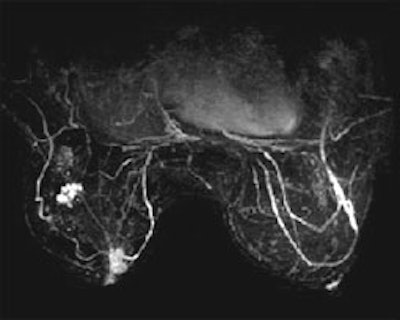

Because of the large amount of data and clinical images produced from breast MRI studies, a truly integrated and effective CAD system is a critical tool for the breast radiologist. AuroraCAD also presents simultaneous axial, sagittal and coronal views of any acquisition or post-processed image set using multi-planar reconstruction. The AuroraCAD allows for side-by-side comparison of pre-and post-contrast images, subtractions, 3D projection images, enhancement curves and more.

See the difference in these SpiralRODEO™ 3-D images: